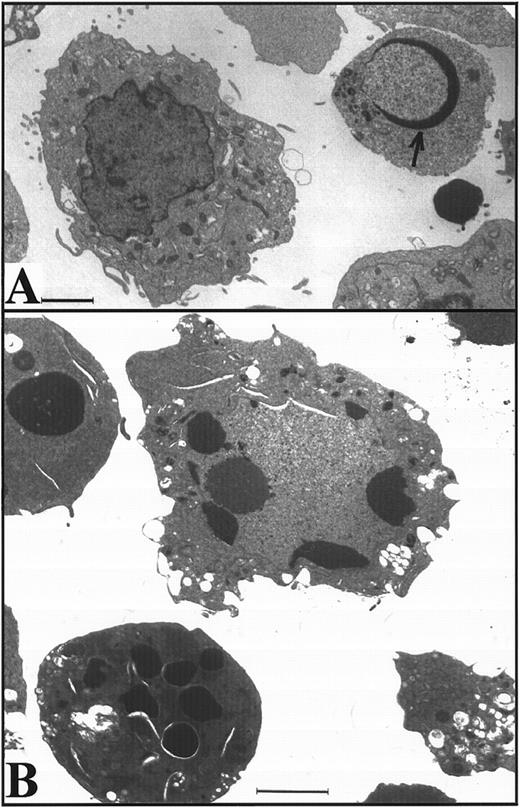

Apoptosis is delayed in K562 cells even after treatment with higher doses of etoposide.The long latent phase and lack of synchrony after treatment of K562 cells with 17 μmol/L etoposide made it difficult to perform additional biochemical studies under these conditions. Previous studies have indicated that increasing the etoposide concentration to 68 μmol/L, a concentration that is readily achievable in the bone marrow transplant setting,61,62 results in more synchronous induction of apoptosis in HL-60 cells, with greater than 85% of cells exhibiting apoptotic morphology within 6 hours.32 When this same strategy was applied to K562 cells, a population of cells with condensed peripheral chromatin was visible at 24 hours (arrow, Fig 3A). At 48 hours, 80% of cells displayed increased electron density (indicating loss of H2O) and peripheral chromatin condensation or nuclear fragmentation when examined by light (not shown) or electron microscopy (Fig 3B). Oligonucleosomal DNA degradation (Fig 3C) as well as proteolytic cleavage of PARP and lamin B1 (the latter detected as loss of intact 67-kD polypeptide in Fig 3D) were readily evident 48 hours after addition of etoposide. Collectively, these observations again indicated that K562 cells demonstrate typical apoptotic changes, although their development was markedly delayed relative to HL-60 cells.

Apoptosis in K562 cells treated continuously with 68 μmol/L etoposide. (A and B) Morphology of K562 cells after 24 hours (A) and 48 hours (B) continuous exposure to etoposide. Arrow in (A), peripheral chromatin condensation in K562 cell after 24-hour etoposide exposure. Bar, 2 μm. (C and D) HL-60 cells treated with etoposide for 0 to 6 hours (lanes 1 through 6) and K562 cells treated with etoposide for 0 to 48 hours (lanes 7 through 10) were harvested for agarose gel electrophoresis (C) and SDS-PAGE followed by blotting with C-2-10 anti-PARP or polyclonal anti-lamin B1 antibodies (D). Arrow indicates 89-kD cleavage product of PARP.